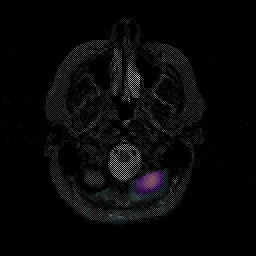

Glioblastoma multiforme overlay -- Slice #8

[Home][Help][Clinical][Tour 1][Tour 2][Tour 3] Slice 8